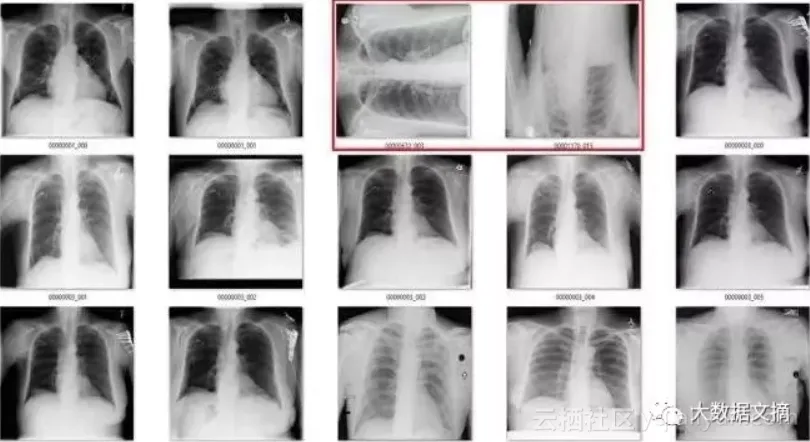

为了说明这一点,我们来看一个来自CXR14的简单例子。在数据集中的正常胸部X射线中,有一些图像经过旋转(这些旋转并未标识在标签中,因此我们不知道哪些是旋转过的)。它们有可能被左右旋转了90度,或180度(颠倒)。

所以,我们的最后一步是在整个数据集上运行模型,进行预测,然后根据预测结果排除那些旋转的图像。由于数据中被旋转过的图像很少,所以我可以一张张检查那些被预测为异常的图像。

该模型一共标记出了171个“旋转”的图像。有趣的是,它实际上作为一个“异常”检测器,识别出许多在非胸部X光的图像。这也不难理解,因为这个模型可能是在学习解剖学的标志。任何异常的东西,如旋转的图像或者是其他身体部位的X射线图像,都不具有正常图片应有的特征。真是意外收获!

在171个被标记为“旋转“的图像中,有51个是实际上旋转过的正面胸部X射线图像。鉴于图片旋转发生的概率非常低(120,000个案例中有51个),这已经是极低的假阳性率。

在余下的120个图像中,56个并不是正面胸片。其中主要包括了侧面胸片和腹部X光片,这也是我想要清理出去的异常图片。